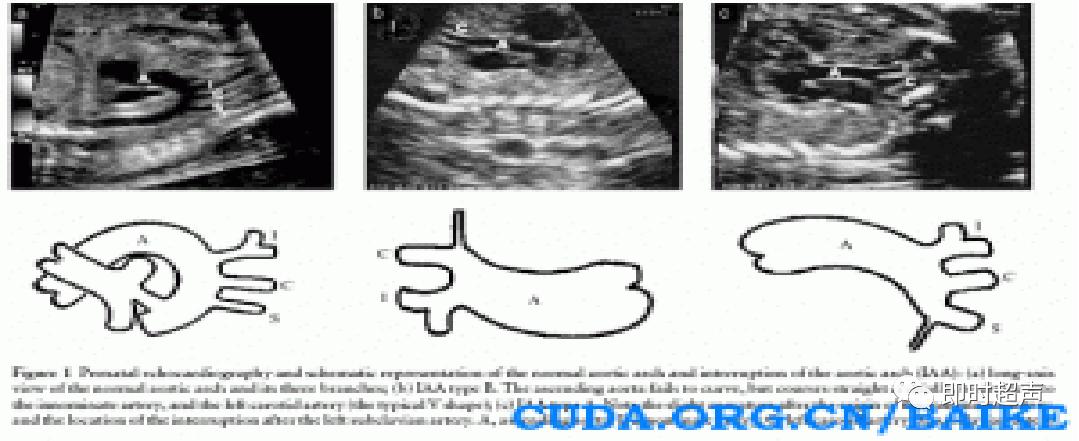

主动脉弓离断

主动脉弓离断定义:升主动脉与降主动脉之间的主动脉弓离断,下肢血供通过动脉导管由右心提供。分类主要根据中断位置与头臂血管的相对关系。A型:左锁骨下动脉远端中断。B型:左颈总动脉远端中断。C型:头臂干远端中断。